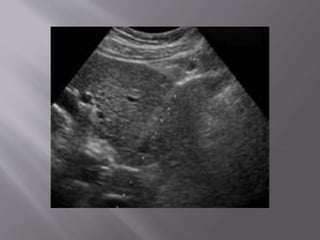

Indications:



Biopsy of a focal solid lesion /suspicious cystic

lesion for diagnosis.

Nonfocal biopsy to evaluate for nephropathy

or renal transplant rejection

US has the advantages of real-time needle

placement

No radiation & is therefore well suited for most

nonfocal renal biopsies in thin pts and in biopsies

of some focal solid masses or cystic masses .

The patient is placed in the prone position and

the biopsy is typically taken from the lower

pole of the kidney if there are no specific

locations of interest.

The biopsy needle is guided using ultrasound

to ensure visualization of the needle as it

pierces the kidney parenchyma.

Care is taken not to enter the collecting system

(as it would result in haematuria) or to go near

the renal hilum (to prevent injury to the

vessels).